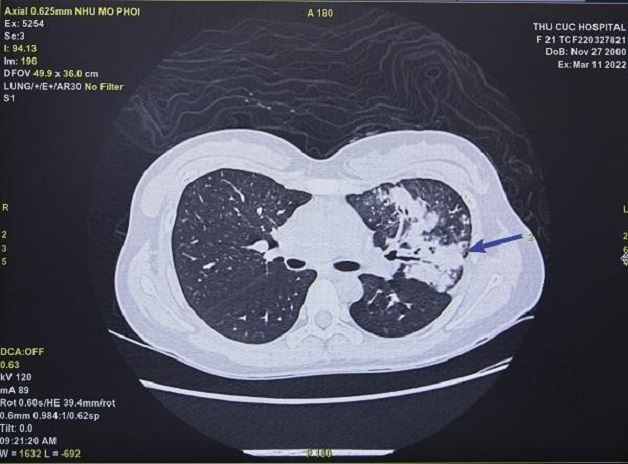

HÌnh ảnh chụp cắt lớp phổi phát hiện tổn thường dạng kính mờ và xơ hóa phổi trên phim chụp CT.

Hình ảnh chụp cắt lớp vi tính phổi của BN đến khám hậu COVID-19 tại Thu Cúc TCI.